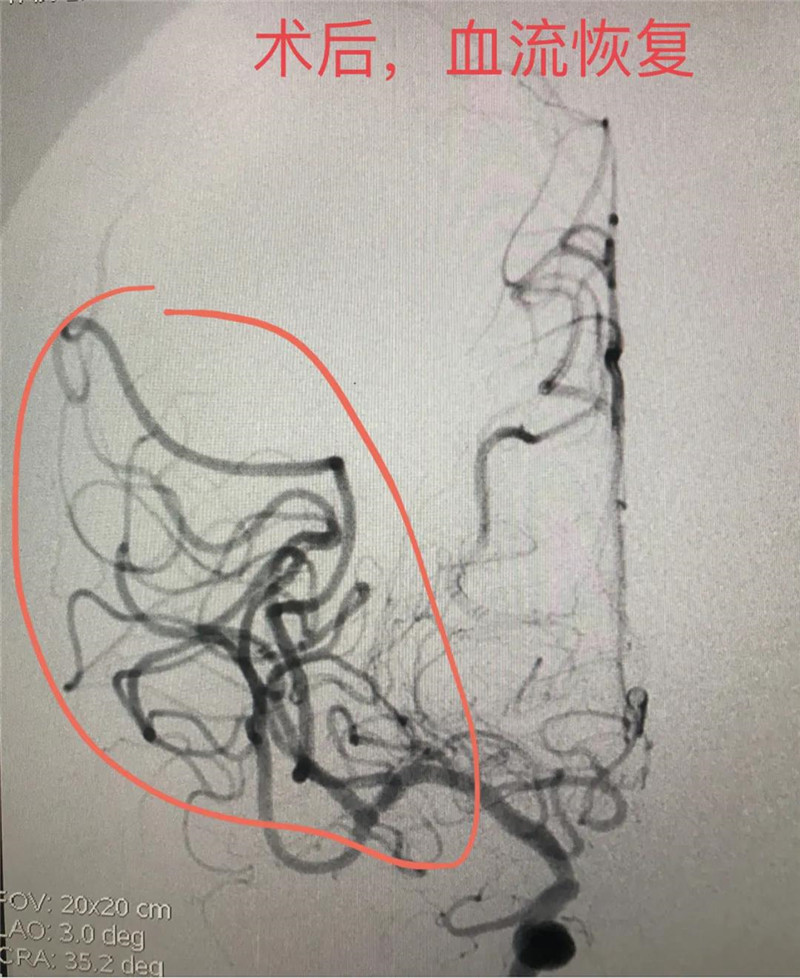

获家属同意后,神经内科专家团队在DSA介入室积极配合下开始了取栓手术。穿刺、造影、取栓,手术非常顺利。完成取栓后,李叔当场便清醒过来,之前无法抬起的左手便恢复了自由。随后,李叔被转入神经内科。后续的治疗和康复中,李叔在神经内科医护人员耐心、细致的治疗和护理下康复出院。对于神经内科医护人员的精心治疗,李叔和家人也都十分感动,于是便出现了7月初李叔送锦旗的事情。